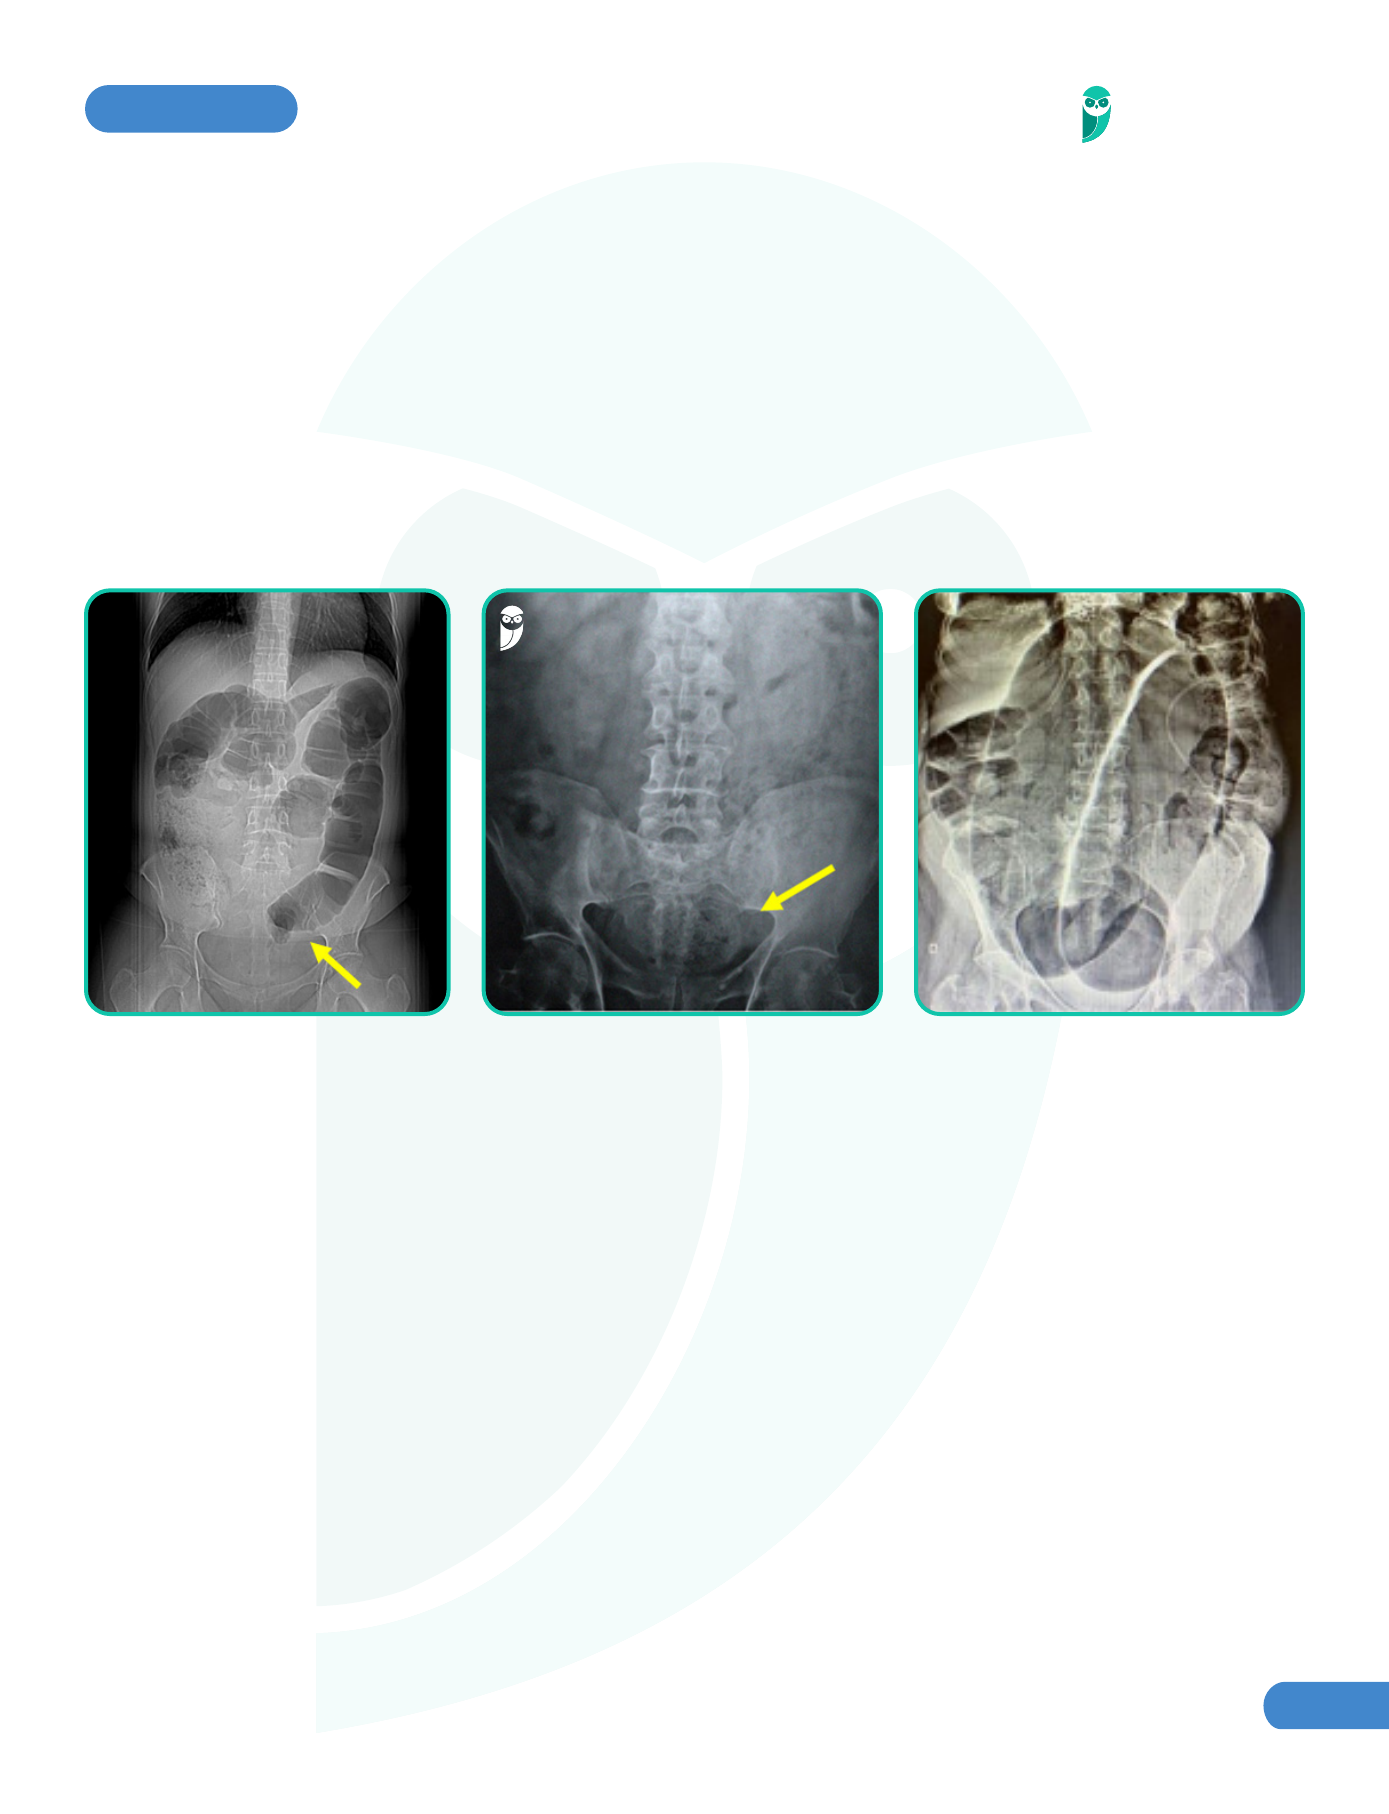

Anomalias Gastrointestinais Pediátricas | Concise Medical Knowledge

image size: 800x1167